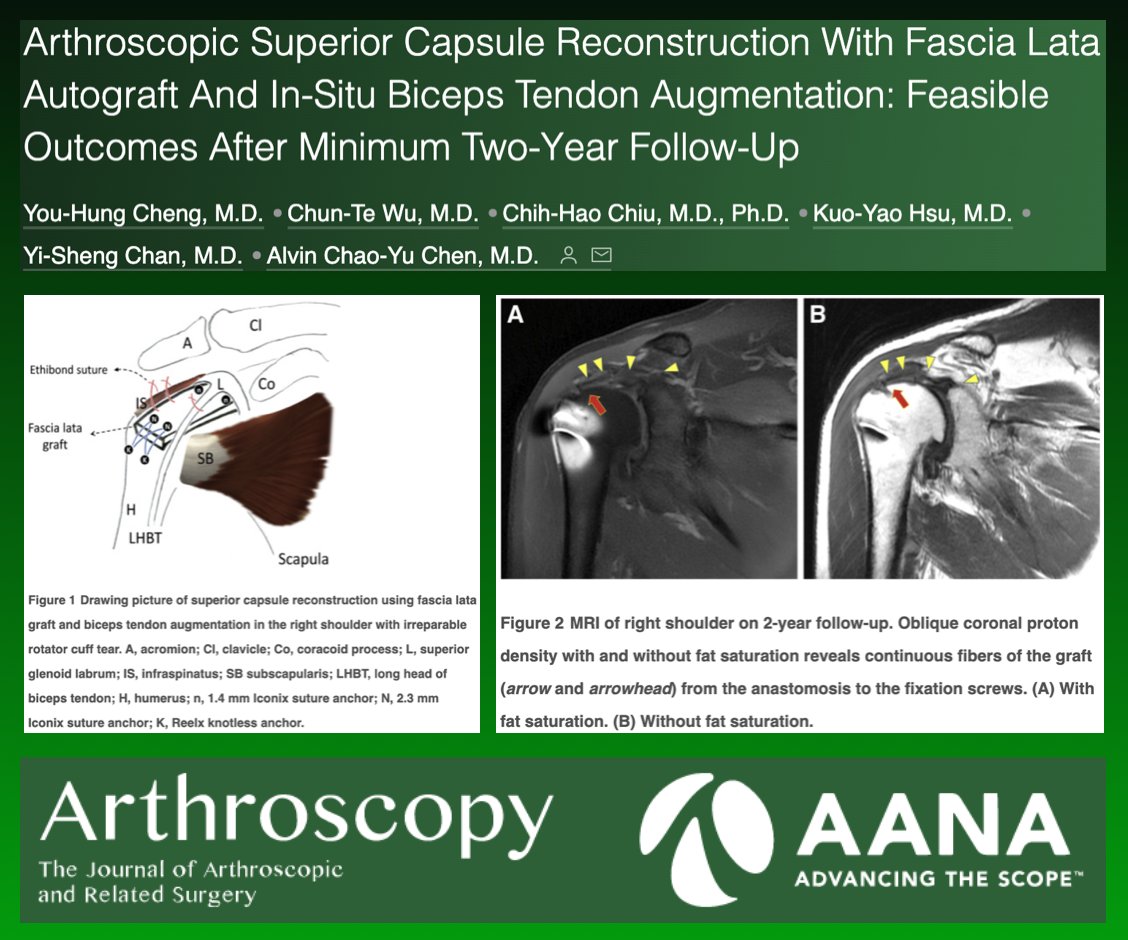

This month's infographic on dermal allograft augmentation of rotator cuff repairs. ow.ly/SMvl50LJ4WR Patrick Denard, M.D